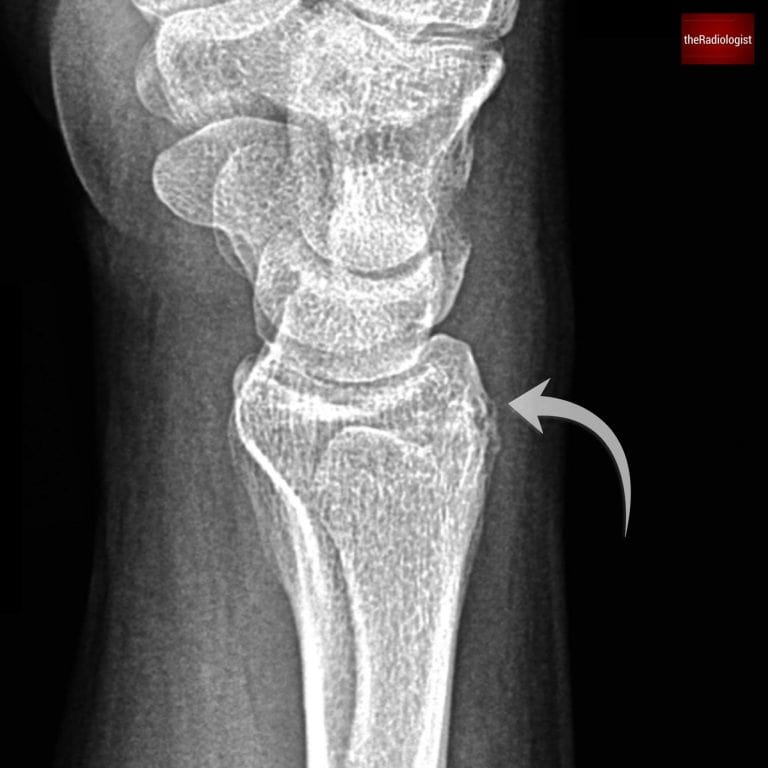

8. Radius and ulna

Finally, assess the distal radius and ulna. Look for cortical breaks or fracture lines, and check the relationship of their articular surfaces: the articular surface of the ulna should not sit distal to that of the radius. If it does, think about an impacted distal radial fracture or possible injury to the distal radioulnar joint. Ensure the distal radioulnar joint is intact and the radius and ulna are not separated: in the context of a radial fracture this could represent a Galeazzi fracture.

Scrutinise the distal radius and ulna looking for a break in the cortex or any suggestion of a fracture line which can be subtle. Here there is a distal radius fracture.